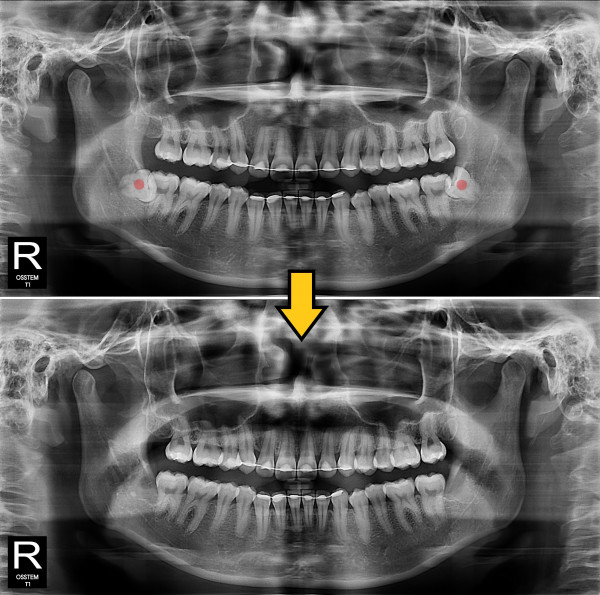

사랑니발치 완전 매복 사랑니